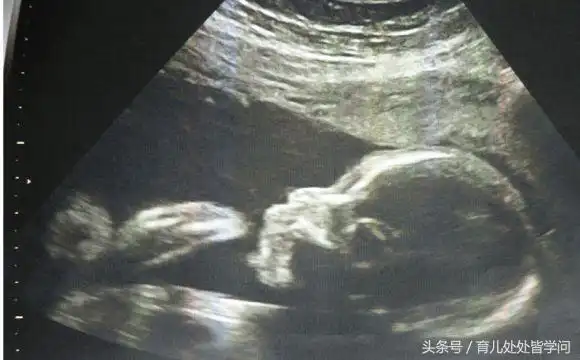

b超看男女应该这么看 重要部位一眼就看出来

b超单子上有男女暗示吗?教你如何看胎儿性别